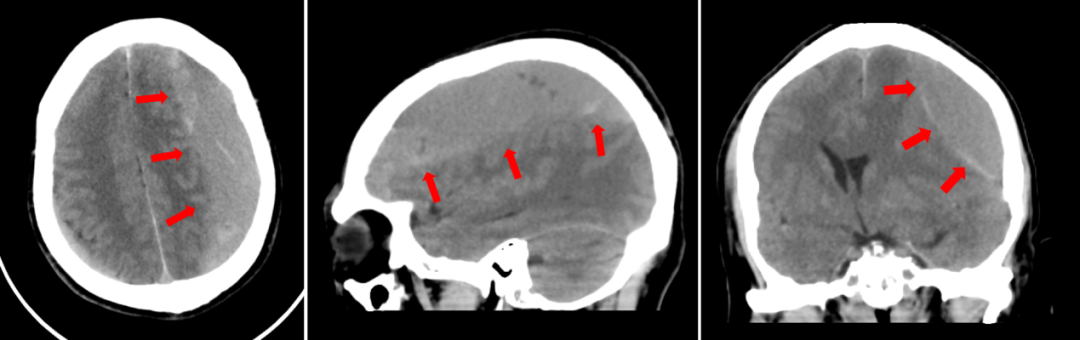

术前CT

患者由社区安排急救车转运至院过程中,医院副院长魏来、医管部部长谢志毅统筹神经外科、麻醉科、手术室、护理团队及隔离病区等相关人员,先行完成发热门诊楼内急救物品、环境准备。中午,患者转运至清华长庚医院发热门诊楼,完善CT等检查后明确:患者为颅内出血、颅内高压、脑组织受压位移等问题,需立刻手术。负压手术室内,由郭毅指导,神经外科主治医师张培海主刀,主治医师刘东康、医师满韦韬辅助,经钻孔、引流管放置、多角度生理盐水冲洗等环节后,用时一小时,手术顺利结束。

术后患者转至发热门诊楼隔离病房,复查CT结果显示颅内血肿清除干净,患者精神状态也同步好转。“感谢你们这么快速地反应,及时给我父亲手术!”患者家属激动地说。“如果发生脑外伤,即便当下没事,也要警惕迟发颅内出血风险,也就是咱们医学上说的慢性硬膜下出血。”张培海提醒道。慢性硬膜下血肿一般出现在外伤后三周到三个月之间,特别是60岁以上老年人群、长期口服阿司匹林的抗凝人群需要注意。